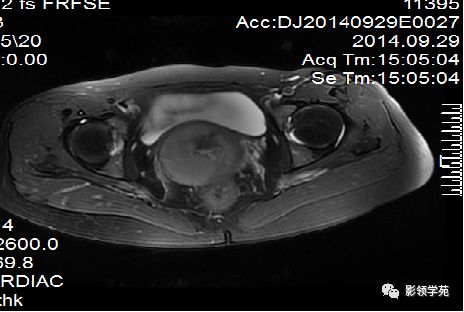

正常MR表现:卵巢和输卵管

卵巢:轴位和冠状面显示较佳,T1WI为中等或稍低信号,T2WI可因多个卵泡结构表现为高信号,但其间质部分仍呈稍低信号

MRI多方位成像应用